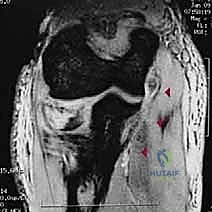

- الأشعة السينية (X-rays): يتم أخذ صور بأوضاع مختلفة (أمامي خلفي، جانبي، ومائل) لرؤية الكسر بوضوح. أحياناً يكون الكسر دقيقاً جداً ولا يظهر إلا من خلال علامة "وسادة الدهون المرفوعة" (Positive Fat Pad Sign) التي تشير إلى وجود نزيف داخل المفصل.

- الأشعة المقطعية (CT Scan): في حالات الكسور المفتتة أو المعقدة، يطلب الدكتور هطيف إجراء أشعة مقطعية ثلاثية الأبعاد (3D CT) لبناء تصور هندسي دقيق للكسر، مما يساعده في تخطيط العملية الجراحية واختيار الشرائح والمسامير المناسبة قبل دخول غرفة العمليات.